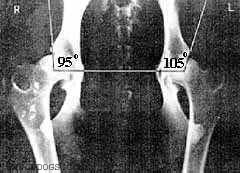

1. Угол Норберга (кранио-ацетабулярный)

измеряется между прямой линией,

соединяющей геометрические центры

головок бедра и линии, проведенной от

центра головки вдоль передне-наружного

края суставной впадины. Разметка

рентгенограммы производится,

согласно методике, специальным

планшет-транспортиром, с последующим

измерением угла обычным

транспортиром.

Нормальный тазобедренный сустав

имеет следующие признаки:

- угол сустава (угол Норберга) 105

градусов и более, часто до 115-125

градусов;

Дисплазия 1 степени:

- угол Норберга 100-105 градусов;

- уплощение в области переднего края

впадины;

- нежные напластования на шейке

бедренной кости;

- еще нормальная фиксация головки

бедра;

- суставные поверхности конгруэнтны,

но щель несколько расширена.